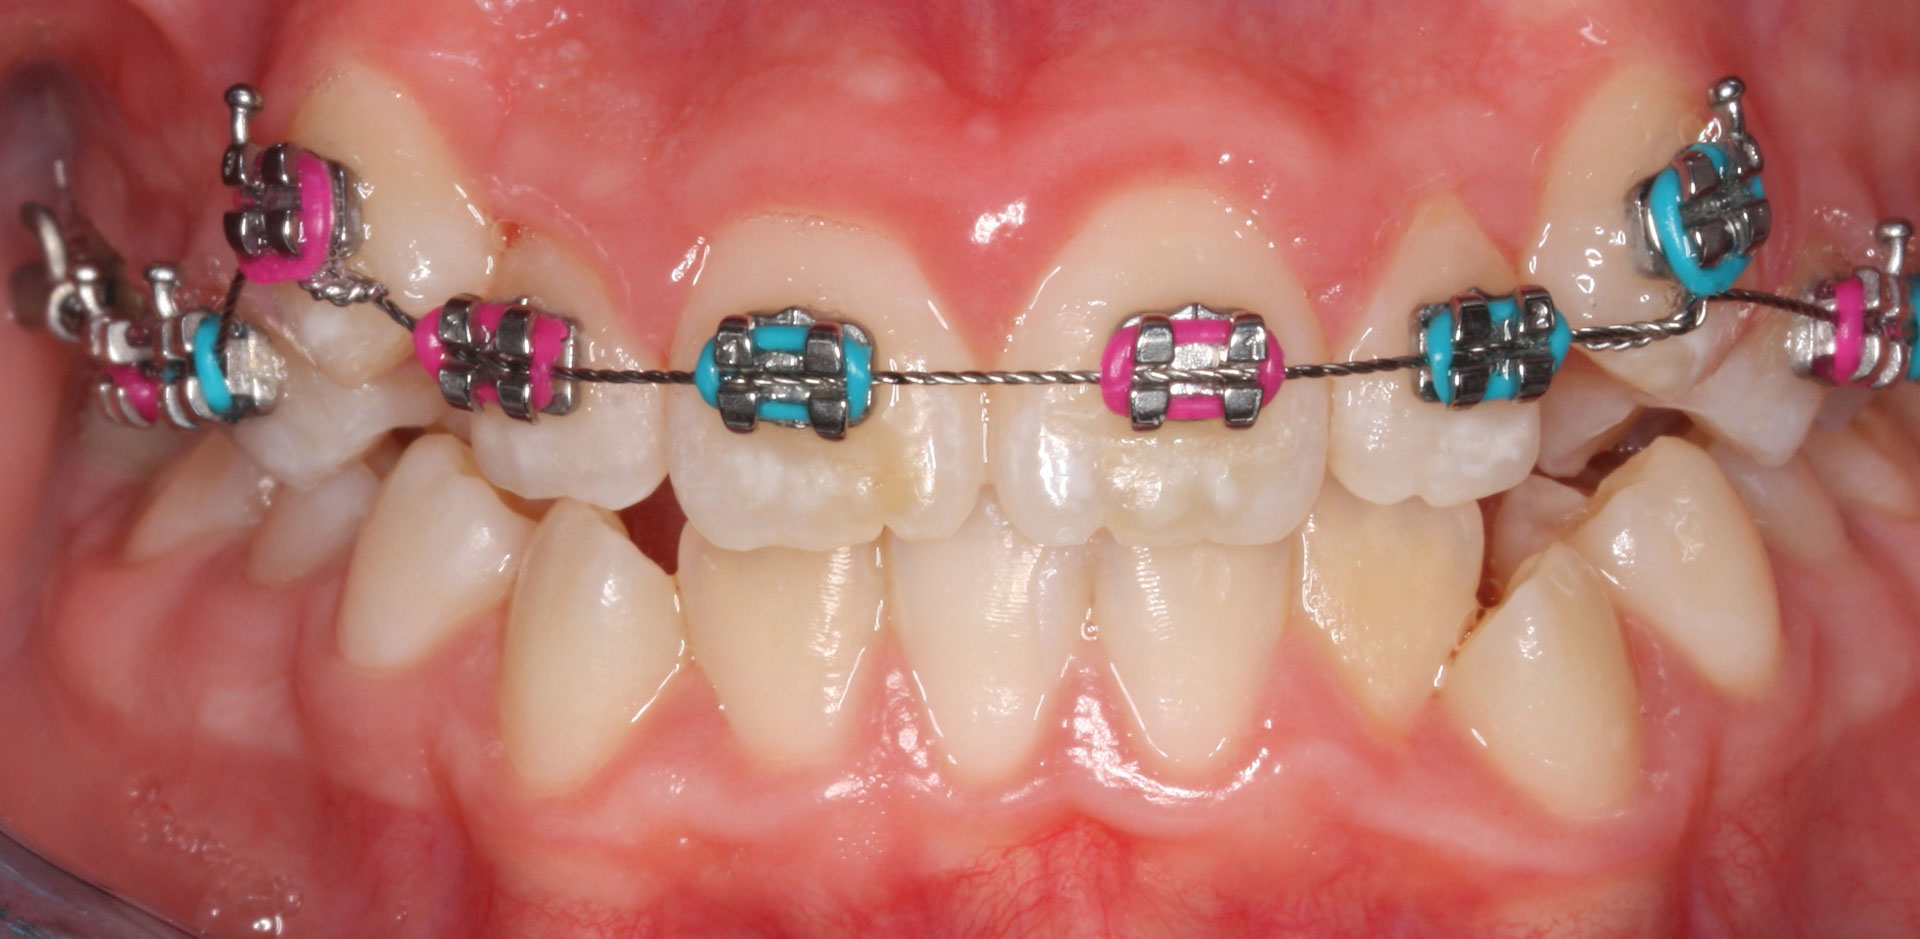

Ortodoncia fija

Caso clínico de apiñamiento severo tratado con brackets de zafiro